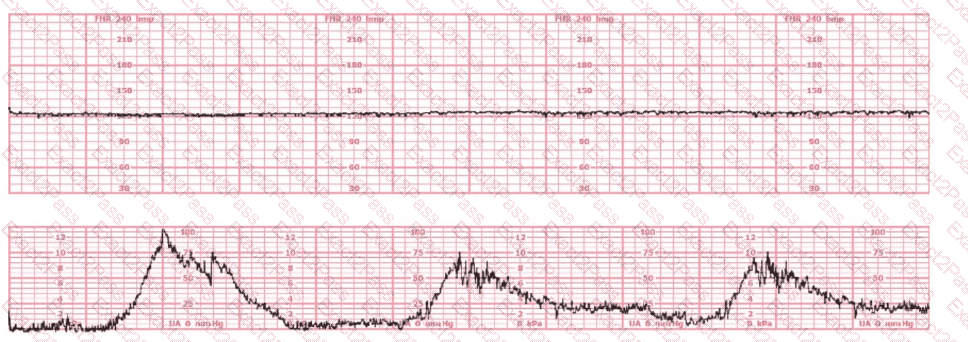

The most probable underlying fetal physiologic cause for this tracing would be:

The tracing shown is from a woman at 28-weeks gestation in the post-anesthesia care unit (PACU) after an appendectomy. She is alert and awake. Based on this fetal heart rate pattern, the most appropriate intervention is:

What is the appropriate interpretation of this tracing?